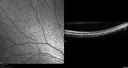

12 year old female She went last December for her regular checkup and spots were noted on the retina in the periphery. Her vision is fine and there is no family history of retinal disease. She has difficulty seeing at night and finding her way in a dark theater. VA OD: Dcc20/20-1 NccJ1+ VA OS: Dcc20/20 NccJ1+

Fundus Albipunctatusvista 962 veces12 year old female with normal vision. She has 4 siblings all of whom have either white spots or spots on IR. Genetic testing by parents was deferred.00000